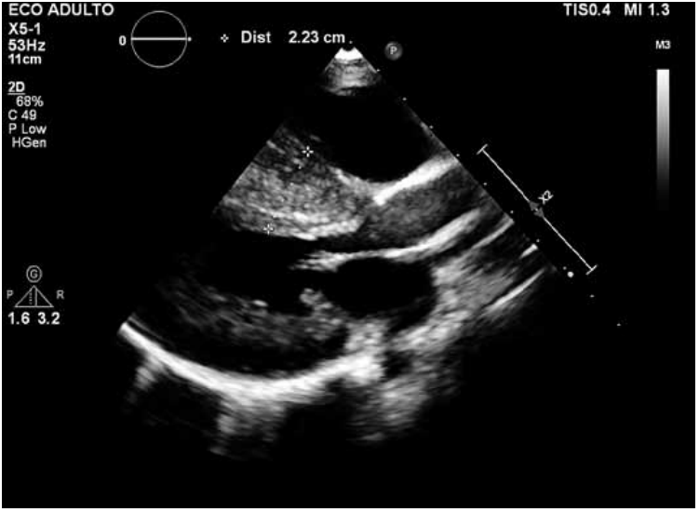

Paciente de 4 anos, masculino, deu entrada no pronto-socorro com cansaço progressivo. Realizou radiografia de tórax, eletrocardiograma e ecocardiograma (figura a seguir).

O diagnóstico que se pode dar a esse paciente é